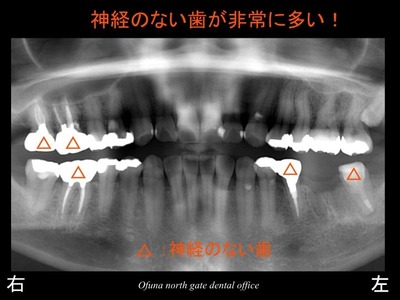

神経のない歯についてはこのブログでもよく紹介してきました。

始めてこのブログを読まれる方のために

簡単に神経のない歯について解説します。

神経のない歯は もろく 通常の咬む力でも割れてしまうことがあります。

こうした状態を患者さんに説明する時に ” 木 ” に例えてお話しすることがあります。

生き生きとした木はたたいたり、

蹴ったりしても折れたりすることはありませんが、

枯れた木は折れる可能性があります。

神経を取った歯も枯れた木と同じような状態になります。

神経のない歯は血液供給がなくなるため 脆く(もろく)なってしまうのです。

この患者様は、神経がない歯が非常に多いことが分かります。

この方も神経のない歯が多いですね。